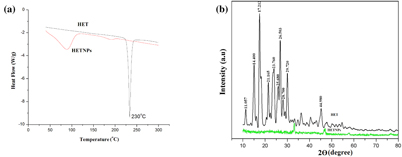

Standard image High-resolution imageDSC and XRD studies are carried out to determine whether the drug was incorporated in the nanoparticulate system as crystalline, amorphous, or bound form. The DSC thermograms demonstrated that only native hesperetin had an endothermic peak of melting point at 230 °C, whereas hesperetin-loaded nanoparticles had no such peak, which showed encapsulated HET to be in either amorphous form or in disordered crystalline phase (figure 5(a)). Furthermore, x-ray diffraction patterns of native HET and HETNPs are present in figure 5(b). Native HET has displayed the characteristic crystalline peaks of 2θ value of 14.400°, 17.212°, 21.165°, 23.760°, 26.503° and 29.720°. However, no characteristic crystalline peaks were observed when the drug was encapsulated in NPs (figure 5(b)). This indicates that the drug was molecularly dispersed or in an amorphous state, which favors easy diffusion of drug molecules through the polymeric matrix, resulting in sustained release of the drug from the nanoparticles. Sustained release of the drug from nanoparticles is an important parameter for developing successful formulations. HETNPs showed a biphasic drug-release pattern that was characterized by an initial rapid release of approximately 29.1% of drugs in the first 8 h, followed by a slow and continuous release of approximately 81.8% drug release in the next 24 h (figure 6). The observed initial release of hesperetin might be due to a rapid release of some drug loosely bound on the surface of the nanoparticles by a mechanism of diffusion. The initial rapid release was followed by a slower sustained release of hesperetin present inside the core of the nanoparticles. A similar trend of release was observed by our previous studies [23].

Figure 5. (a) DSC endothermic curve of native HET and HETNPs and (b) x-ray diffraction (XRD) patterns of native HET and HETNPs.

Characterization of the physiochemical properties of the drug encapsulated within the nanoparticles may possibly reveal useful information for the feasibility of using nanoparticles for cancer therapy. FT-IR results confirmed that drug is encapsulated inside the polymer. DSC results of HET showed a sharp endothermic peak at 230 °C which is the well known melting point of hesperetin, but in the case of HETNPs the melting peak totally disappeared evidencing the absence of crystalline drug in the nanospheres samples, at least at the nanosphere surface level. Therefore, it could be concluded that hesperetin in nanospheres was in an amorphous or disordered crystalline phase of molecular dispersion or a solid solution state in the polymer matrix after the production [38]. Further, this result is very well supported by XRD. Both DSC and XRD results confirmed that HETNPs have amorphous form. Encapsulation efficiency of hesperetin has increased because the hydrophobic portion of PVA interpenetrated into Eudragit chains during nanoprecipitation and remained to be trapped to the polymeric matrix of the nanoparticles. Accordingly, the addition of PVA easily formed an interconnected network with Eudragit-hesperetin and thus elevated the encapsulation efficiency of the drug. In the current study, the initial rapid release of hesperetin from nanoparticles was probably attributed to either the surface-bound moieties or an aqueous environment allowing increased water penetration. Afterwards, the HETNPs manifested the sustained release characteristics that appeared to be dependent on the hydrophobicity of hesperetin incorporated in the nanoparticles. The release pattern of the drug from the nanoparticles shows that long and continuous exposure of the cancer cells to anticancer drugs of a relatively lower and safer concentration gives little chance for the tumor blood vessels to grow, thereby resulting in much better efficacy [39]. Native HET and HETNPs were further evaluated for their in vitro cellular viability assay on KB cell lines by MTT assay. MTT results showed a good discrimination in cell inhibition between native HET and HETNPs, thus illuminating the key role of NPs binding and internalization in enhancement of cytotoxic activity. Encapsulation of anti-cancer drug in nanoparticles can increase its internalization by cells into lysosomes and enhanced cytotoxicity. The higher cytotoxic effect of hesperetin-loaded nanoparticles could be attributed to the competent cellular uptake and intracellular distribution of hesperetin.